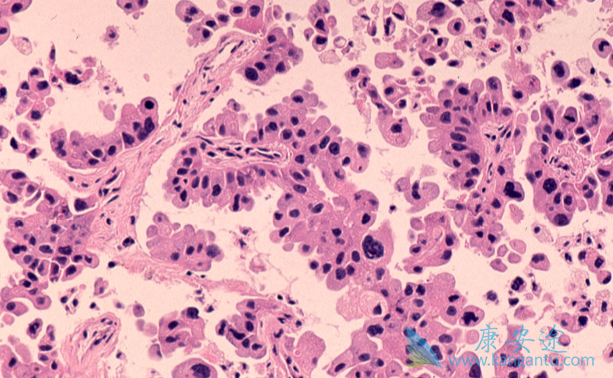

目前针对肺癌患者有很多靶向药物,但是只有携带明确的基因突变的患者才能受益于这些药物,非小细胞肺癌(NSCLC)患者的常规分子检测通常会发现患者携带常见基因突变,比如EGFR或ALK基因突变,之后患者就会接受EGFR或ALK驱动基因突变靶向药物治疗。然而,相比之下,没有携带驱动基因突变的肺腺癌患者的治疗选择要少得多。从根本上来说,这类患者只能选择含铂双药联合化疗,该疗法已有30多年。”